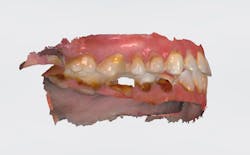

Case review: This 35-year-old female was diagnosed with Sjögren’s syndrome four years ago. She is a cigarette smoker and drinks multiple sodas per day. Her daily oral hygiene is marginal (figures 3–5).